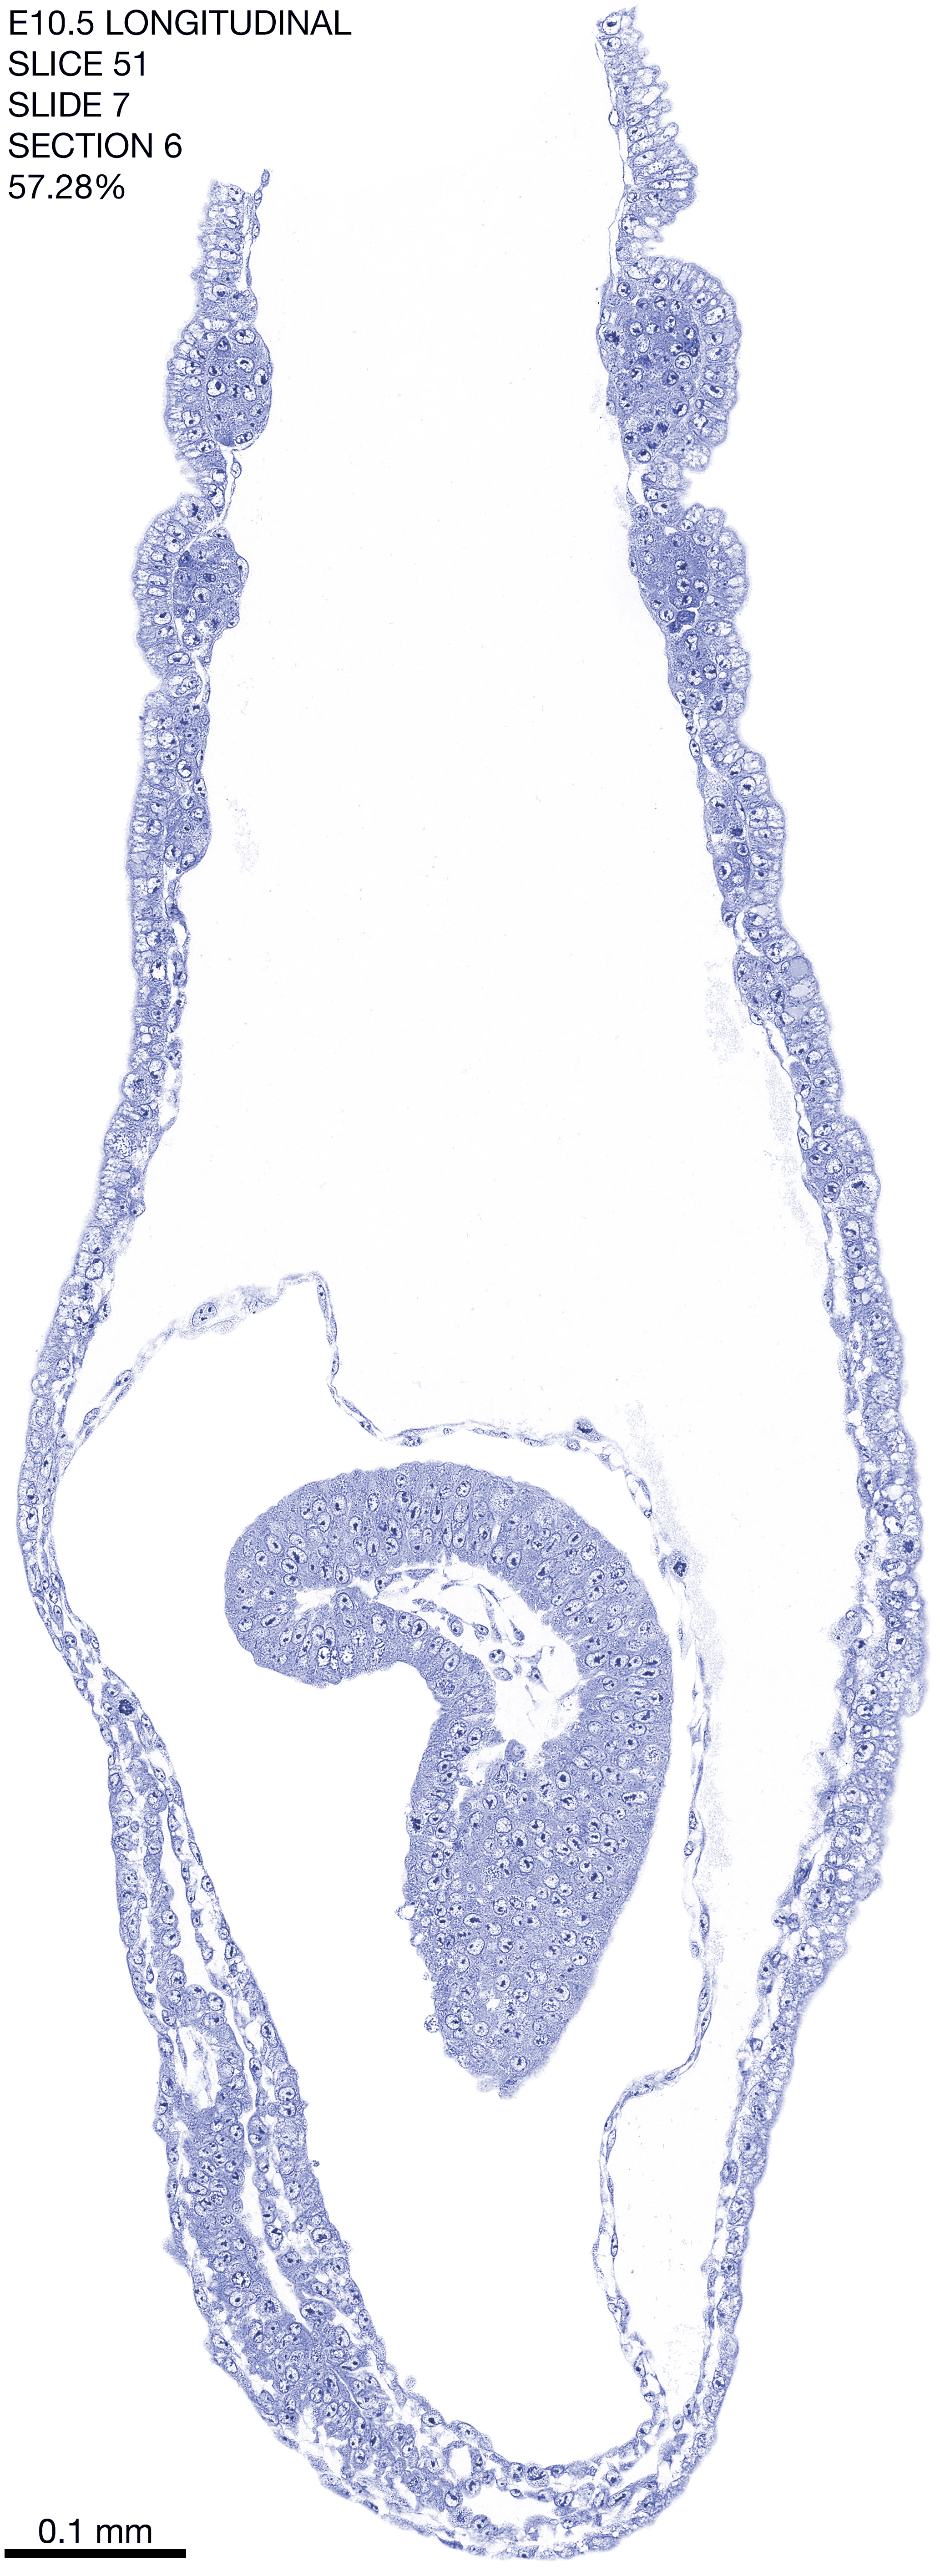

E10.5 Longitudianal Archive This page contains jpg files of ALL SLICES (each 3µm thick) that were scanned of the E10.5 longitudinally cut specimen. Download: Large | High Res Download: Large | High Res Download: Large | High Res Download: Large | High Res Download: Large | High Res Download: Large | High Res Download: Large | High Res Download: Large | High Res Download: Large | High Res Download: Large | High Res Download: Large | High Res Download: Large | High Res Download: Large | High Res Download: Large | High Res Download: Large | High Res Download: Large | High Res Download: Large | High Res Download: Large | High Res Download: Large | High Res Download: Large | High Res Download: Large | High Res Download: Large | High Res Download: Large | High Res Download: Large | High Res Download: Large | High Res Download: Large | High Res Download: Large | High Res Download: Large | High Res Download: Large | High Res Download: Large | High Res Download: Large | High Res Download: Large | High Res Download: Large | High Res Download: Large | High Res Download: Large | High Res Download: Large | High Res Download: Large | High Res Download: Large | High Res Download: Large | High Res Download: Large | High Res Download: Large | High Res Download: Large | High Res Download: Large | High Res Download: Large | High Res Download: Large | High Res Download: Large | High Res Download: Large | High Res Download: Large | High Res Download: Large | High Res Download: Large | High Res Download: Large | High Res Download: Large | High Res Download: Large | High Res Download: Large | High Res Download: Large | High Res Download: Large | High Res Download: Large | High Res Download: Large | High Res